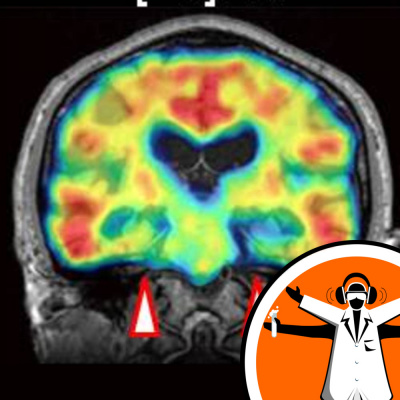

Until recently, it has been extremely difficult to track the progression of Alzheimer's disease, as the neurons of the brain which are affected by the disease are impossible to view directly. However this week a Japanese research group, writing the the Journal Neuron, announced the development of a new radioactive compound which could be used, in conjunction standard medical imaging, to track the progression of Alzheimer's in the brain. Naked Scientist Priya Crosby spoke to lead author on the paper, Dr Makoto Higuchi, to find out more about this exciting new possibility for Alzheimer's... Like this podcast? Please help us by supporting the Naked Scientists